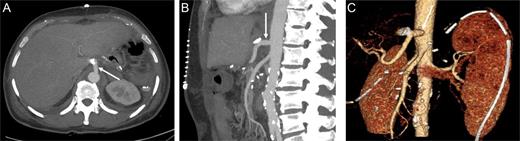

The patient's post-operative hospital stay was uneventful, and control CT demonstrated patent reconstruction (Fig. 5).

Contrast-enhanced CT in the arterial phase after celiac trunk reconstruction: axial (A) and sagittal (B) MIP, and coronal oblique 3D VR images (C) demonstrating patent reconstruction with an iliac graft (arrow).